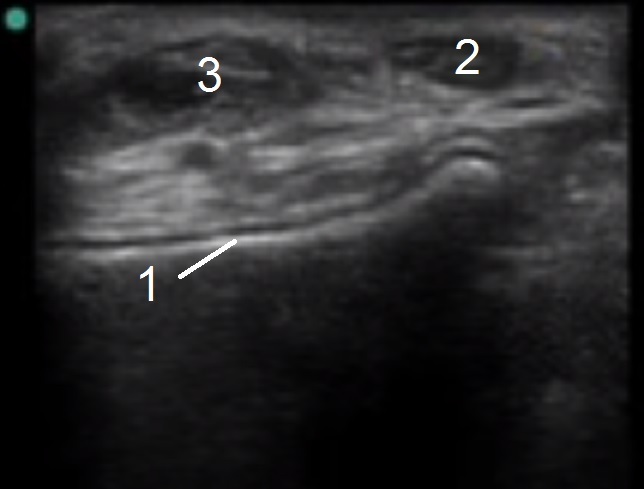

Bild 1: Fuß und Sprunggelenk, Anatomie d. Extensorsehne

1. Talus

2. Sehne d. Tibialis anterior

3. Sehne d. Extensor hallucis longus